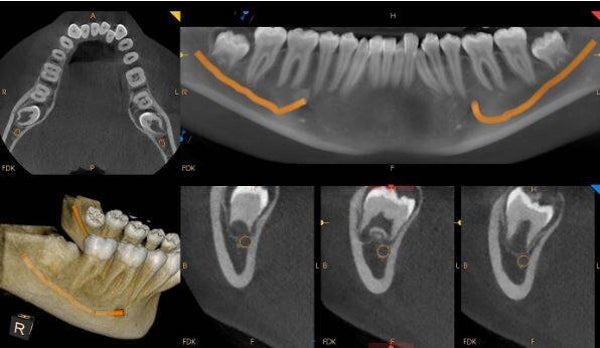

Medium F.O.V CBCT

CA$180.00

Maxilla or Mandible.